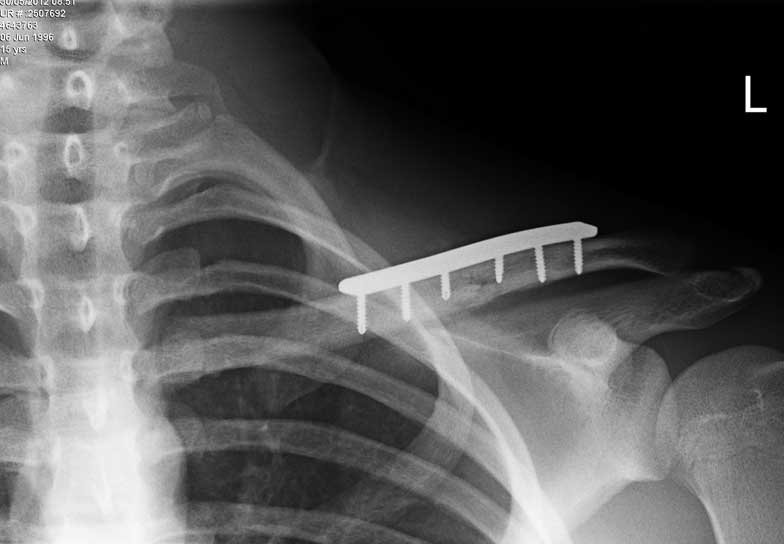

From www.hopkinsmedicine.org

Clavicle Fracture Open Reduction and Internal Fixation Johns Hopkins Medicine Clavicle Fracture Future Problems Most collarbone fractures heal on their own with. Our study revealed that patients with clavicle fractures treated with plate fixation had statistically significant good functional. Midshaft clavicle fractures are common traumatic injuries caused by a direct impact to the shoulder girdle and is most commonly seen in young, active adults. Despite conflicting evidence, most studies indicate that superior clinical results.. Clavicle Fracture Future Problems.

From www.cureus.com

Cureus Surgical Fixation of Clavicle Shaft Fractures Using Superior Locking Plates With Clavicle Fracture Future Problems The clavicle (collarbone) is one of the most fractured bones in the body. Midshaft clavicle fractures are common traumatic injuries caused by a direct impact to the shoulder girdle and is most commonly seen in young, active adults. A fall or a blow to your shoulder can fracture your collarbone (clavicle). Most collarbone fractures heal on their own with. Despite. Clavicle Fracture Future Problems.